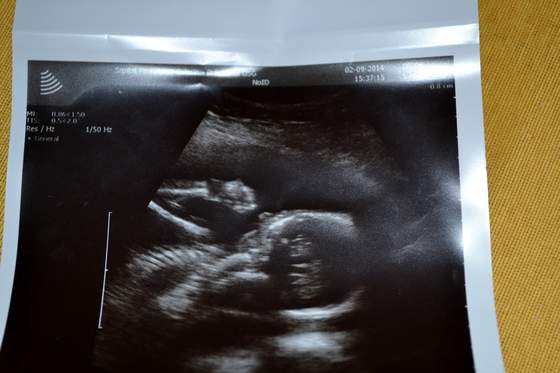

A oto nasze nie do końca zidentyfikowane dziecię :-)

Z profilu i z rączką przy uchu

DSC_0472.jpgDSC_0477.jpg